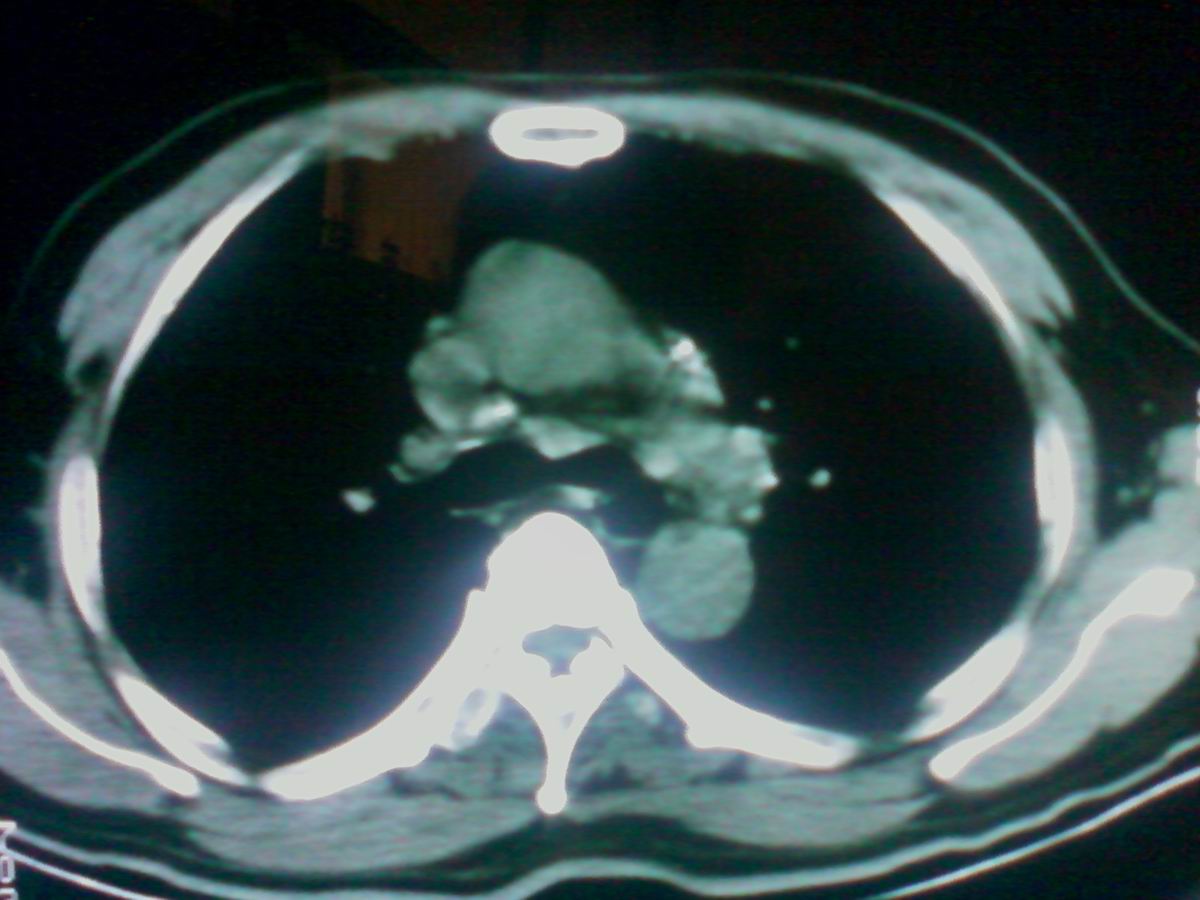

气管后部见半圆形软组织密度病灶,考虑占位,建议气管镜除外鳞癌。

气管上段的肿瘤多为良性乳头状瘤,气管下段的肿瘤多为鳞癌,气管中段的良恶性各占一半。本例位于气管下段,先按恶性处理。不过纤支镜是免不了的。

考虑气管癌可能性大。